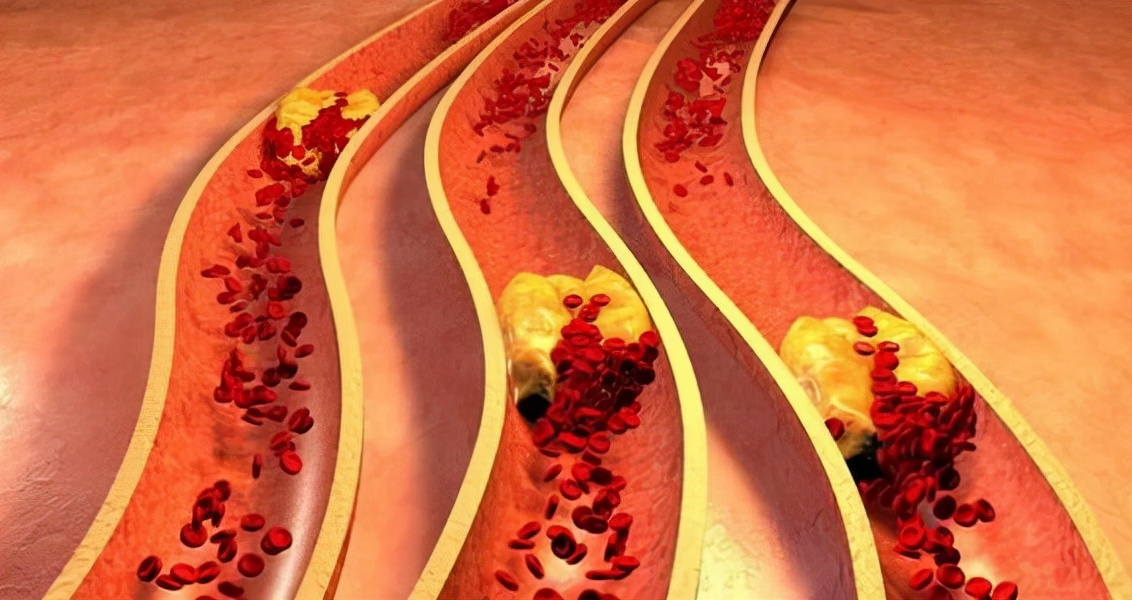

保持血管的健康对人体健康有很大的意义 , 它就像自来水管 , 一旦发生堵塞就会展示不出它的作用 , 不能正常运作 , 影响后续的计划 。 尤其是脑梗和心梗 , 最为危险 , 也是最经常见到的两种血管疾病 。

【睡眠|睡觉有2个表现,多半血管已堵塞,医生:常吃1物,可给血管“洗个澡”】但凡大脑供血、供氧不足 , 就会失去管控权 , 而且大脑内部的血管大部分都是由中小型血管组成的 , 所以更易于受到阻碍淤塞 。 假若血液不能及时畅通 , 就会激发缺血性脑梗 , 严重还会使我们的生命受到威胁 。

而心脏的主要功能就是支撑整个人体的血液输送 , 它就是个血液泵 , 万一体内血管中的杂质过多或过于浓稠时 , 就会降低心脏的工作效率 。 而心脏血管被拥堵会很轻易患上冠心病 , 但凡心肌负荷受到重大压力 , 就很容易使心脏骤停 。